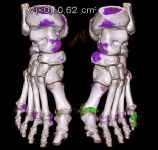

2、双能量CT检查:最常用的检查方式,双能CT伪彩图发现痛风石(绿色结节,如下图)对于痛风的诊断具有重要意义。